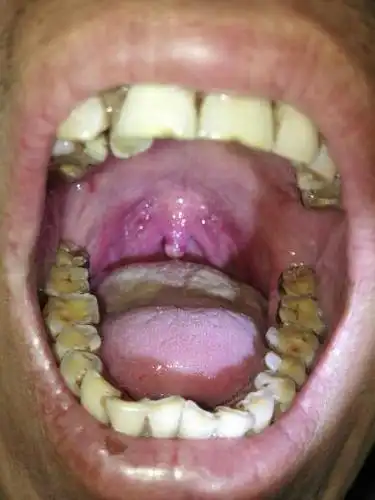

求救 求救求救 懂的医师 专家 麻烦耽误几分钟给我